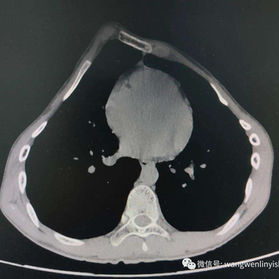

The patient's chest wall protrudes significantly, with the central part being the most pronounced and forming an acute angle deformity. Additionally, there are depressions on both sides of the lower half of the chest wall. The patient was diagnosed with severe complex chest wall deformities.